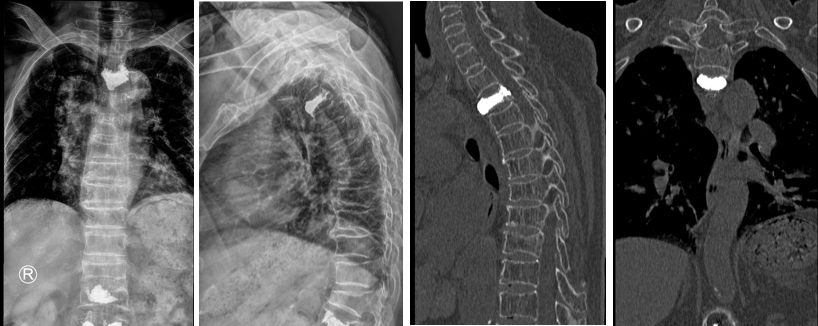

今年85岁的丁老太10天前在家里不小心摔了一跤,当即感到胸背疼痛不适,在家卧床休息数天仍不见好转。由于有过类似经历,丁老太之前摔跤后在当地医院做过椎体注射“骨水泥”的手术,且效果良好,于是家属想着大不了再打一次“骨水泥”就好了。随即到先前的医院检查,确诊是脊柱压缩性骨折,但与以往不同的是,这次是第三胸椎骨质疏松性压缩性骨折。第四胸椎以上由于位置特殊,手术操作难度大、风险高,通常是不做“骨水泥”手术的。当地医院的医生建议老太回家卧床休息保守治疗。随后患者和家属辗转就诊了几家医院,得到的建议都是保守治疗。难忍的疼痛及无法起床使老人陷入了绝望之中。

丁老太入院第三天,姜主任在骨科主治医师蒋伟刚的配合下,成功为其实施了机器人辅助下经皮椎体球囊扩张成形术。术后第一天,患者可以下地活动,疼痛消失;第二天即出院,整个住院时间仅6天,真正做到了术后快速康复!丁老太的女儿感慨道,庆幸有独墅湖医院骨科姜主任和他的团队的出手相助,再加上手术机器人辅助,才帮助老人家过了这一关!

椎体强化术是治疗骨松性椎体压缩性骨折的有效手术方法,其中使用最多的是椎体后凸成型术,简称PKP术。随着科技的进步,过去通常无法实施的部位也可以施行该手术。手术效果立竿见影,这一技术使许多老年患者摆脱了难以忍受的痛苦,挽救了他们的生命。